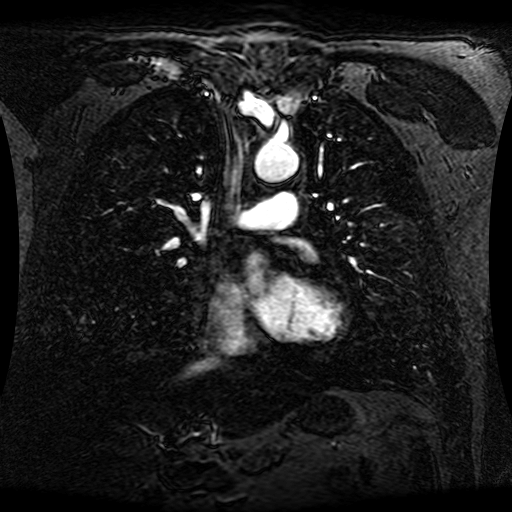

Data Description

These magnetic resonance angiography (MRA) images show coronal slices acquired from consecutive anteroposterior positions within the torso. The study was performed on a 1.5T General Electric (GE) Signa imaging system with gadolinium-contrast-enhancement for visualization of the cardiopulmonary vasculature. The pulse sequence used was a 3D time-of-flight fast spoiled gradient recalled acquisition in steady state (FSPGR, TR=6.3, TE=1.4, NEX=1, FOV = 40cm, slice thickness = 1.2mm).

This sample image contains 76 frames. It is available in DICOM format (E1154S7I.dcm), as an animated GIF (E1154S7I.gif), as .ogg, .mp4, .webm, and .swf animations (one of which is shown above), or as individual PNG-format frames (see below).